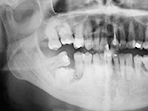

図❷ 初診時、パノラマX線写真

パノラマX線写真所見:6相当骨体部に、不整形な粒状~突起状の石灰化物を伴う6と考えられる歯牙様不透過像を認めた(図❷)。